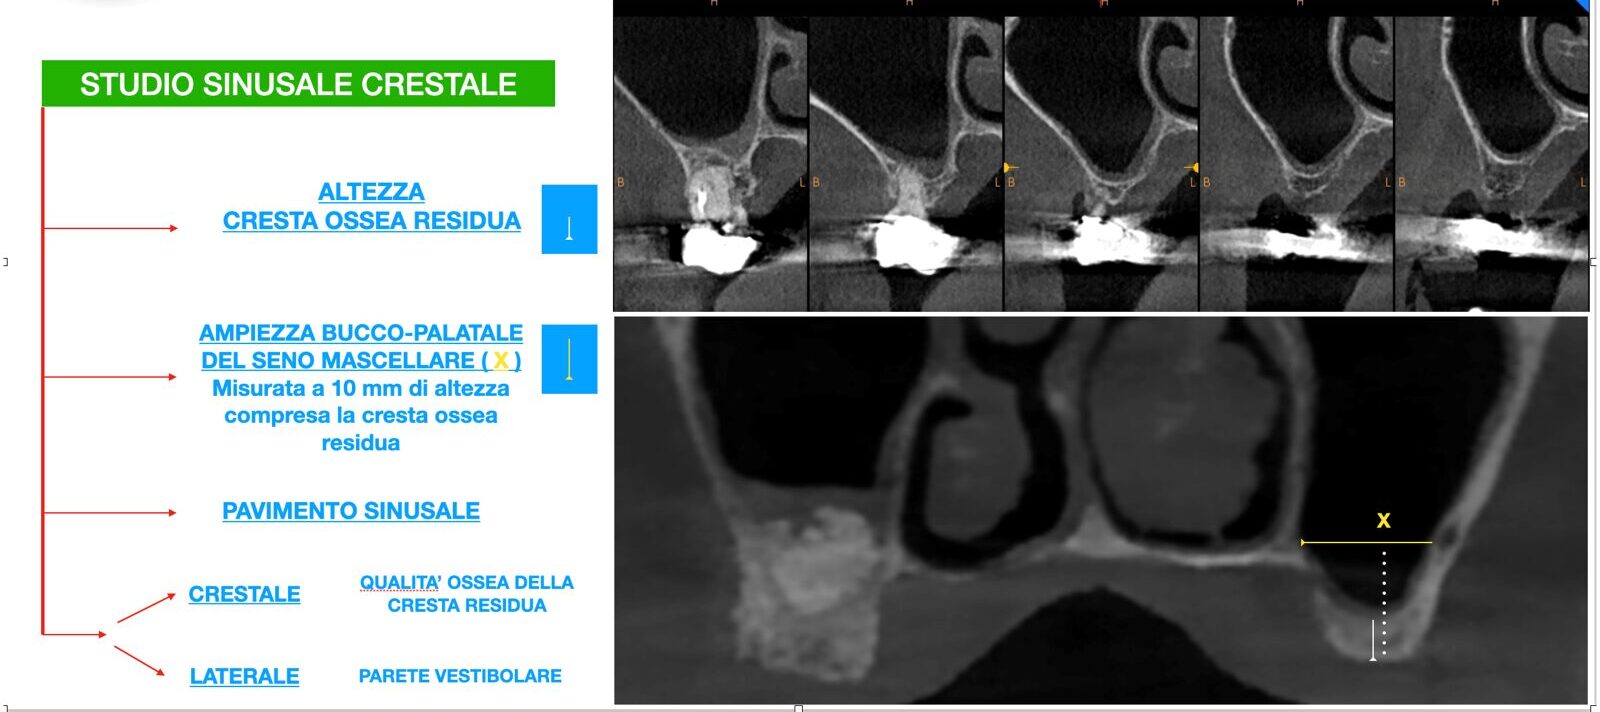

• INDAGINI DIAGNOSTICHE RADIOGRAFICHE

• PIANIFICAZIONE E TECNICHE CHIRURGICHE DEL RIALZO DI SENO MASCELLARE (MINI E GRANDE)

• PIANIFICAZIONE DEI CASI CLINICI DA OPERARE